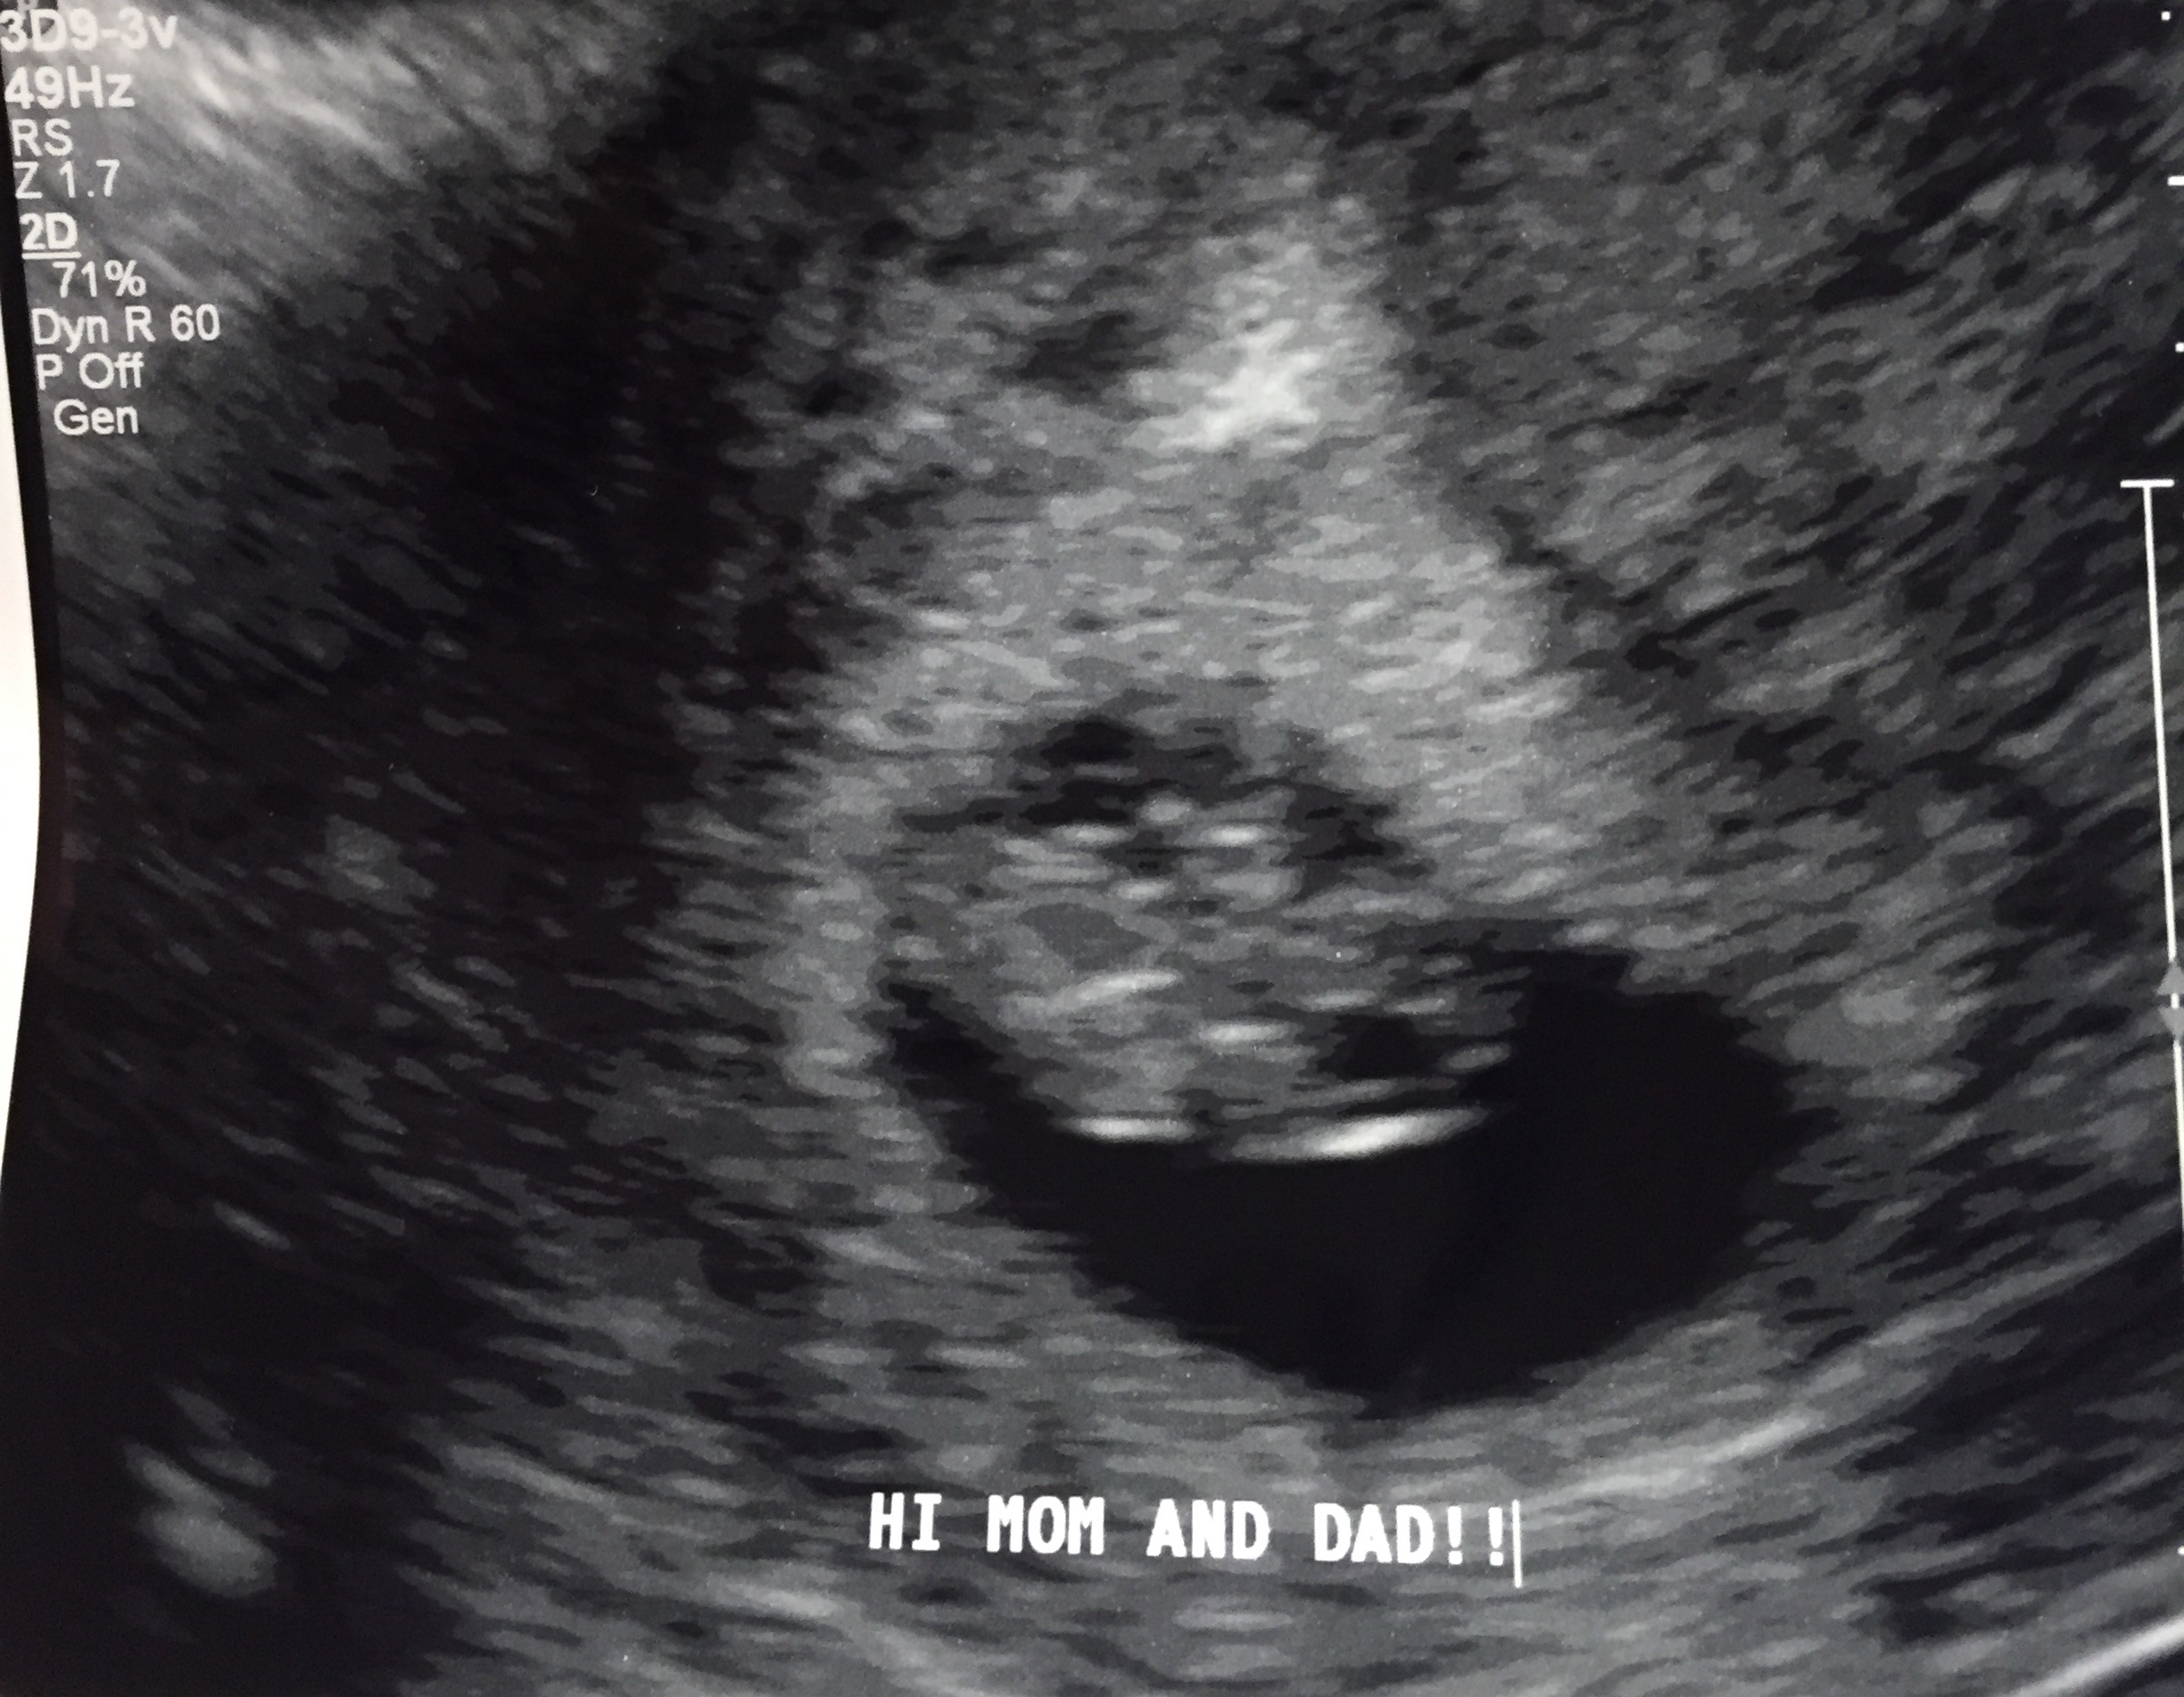

My first ultrasound pic at 9w3d. Measured a few days small. Doctor pointed out that I had twins, but one was not able to stick around We're sad about this, but we're thrilled to see our other healthy little baby! So in love!